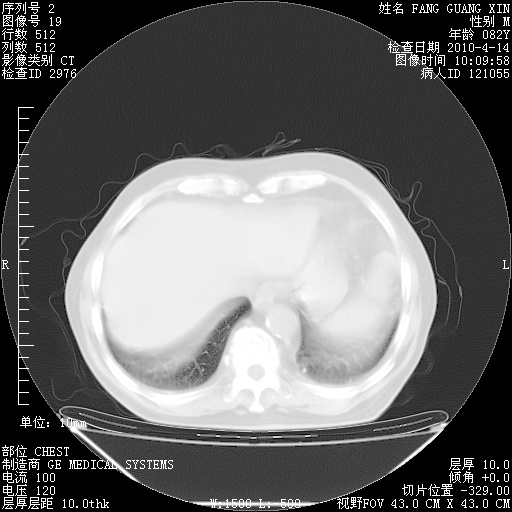

4月14日肺部CT

肺部CT平扫未见异常。